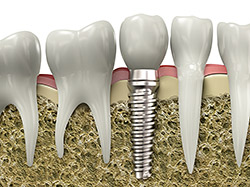

Implant Restoration

If you have missing teeth, it is crucial to replace them. Without all your teeth, chewing and eating can destabilize your bite and cause you discomfort. When teeth are missing, your mouth can shift and even cause your face to look older. Implants are a great way to replace your missing teeth, and if properly maintained, can last a lifetime!

An implant is a new tooth made of metal and porcelain that looks just like your natural tooth. It’s composed of two main parts: One part is the titanium implant body that takes the place of the missing root, and the second part is the tooth-colored crown that is cemented on top of the implant. With periodontal treatment, you can smile confidently knowing no one will ever suspect you have a replacement tooth.

In addition to tooth replacement, implants may be used to anchor dentures, especially lower dentures that tend to shift when you talk or chew. For patients with removable partial dentures, implants can replace missing teeth so you have a more natural-looking smile.